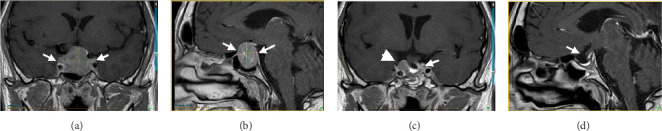

背景:促甲状腺激素(TSH)分泌型垂体腺瘤(TSHomas)是一种非常罕见的垂体肿瘤,可引起中枢性甲状腺功能亢进。大多数为大腺瘤(≥10mm),诊断时伴有局部和全身合并症。甲状腺功能试验(TFTs)的不典型变化可能是微妙的,最初常常被遗漏,而其他垂体激素的过度分泌往往存在。生长抑素类似物(SSAs)是推荐的一线药物治疗这些病变。我们报告两例TSHomas成功地管理与多巴胺激动剂(DA)治疗,单独或后经蝶窦手术(TSS)。病例介绍:一名47岁男性,表现为体重明显减轻、疲劳和肌肉无力。他被发现有高泌乳素血症、继发性肾上腺功能不全(AI)和中枢性性腺功能减退,导致发现一个3厘米的侵袭性垂体腺瘤。额外的测试显示IGF1, TSH和游离T4增加。经TSS部分切除后病理证实为Pit-1多激素肿瘤。持续的高催乳素血症和中枢性甲状腺功能亢进对DA治疗有反应,因为患者拒绝治疗。66岁男性,有焦虑、高血压、冠状动脉疾病、房颤、甲状腺结节病史,因严重头晕就诊,头部CT扫描发现垂体腺瘤2.4 cm。实验室记录显示,在过去的五年中,游离T4和TSH逐渐异常增加。他拒绝手术,对DA治疗有很好的临床和生化反应。结论:通过长期监测和正确解释TFT,及时发现中枢性甲状腺功能亢进,对tshoma的早期诊断和最佳治疗至关重要。分泌tsh的腺瘤可能对DA治疗有反应。

Background: Thyroid-stimulating hormone (TSH)-secreting pituitary adenomas (TSHomas) are very rare pituitary tumors causing central hyperthyroidism. Most are macroadenomas (≥ 10 mm) with local and systemic comorbidities at diagnosis. The atypical changes in thyroid function tests (TFTs) may be subtle and are often initially missed, while over-secretion of other pituitary hormones is often present. Somatostatin analogs (SSAs) are the recommended first-line medical therapy for these lesions. We report two cases of TSHomas successfully managed with a dopamine agonist (DA) therapy, alone or following transsphenoidal surgery (TSS). Case Presentation: A 47-year-old man presented with significant weight loss, fatigue, and muscle weakness. He was found to have hyperprolactinemia, secondary adrenal insufficiency (AI), and central hypogonadism, which led to the discovery of a 3 cm invasive pituitary adenoma. Additional tests showed an increased IGF1, TSH, and free T4. A Pit-1 multihormonal tumor was documented on pathology after partial resection by TSS. Persistent hyperprolactinemia and central hyperthyroidism responded to DA therapy, as the patient refused therapy. A 66-year-old man with a history of anxiety, hypertension, coronary artery disease, atrial fibrillation, and thyroid nodules, was consulted for severe dizziness and was found to have a 2.4 cm pituitary adenoma on a head CT scan. Lab records showed a progressive supranormal free T4 and TSH increase over the preceding five years. He refused surgery and had an excellent clinical and biochemical response to DA treatment. Conclusion: Prompt detection of central hyperthyroidism by monitoring and correctly interpreting TFT over time is essential for early diagnosis and optimal management of TSHomas. TSH-secreting adenomas may respond to DA therapy.